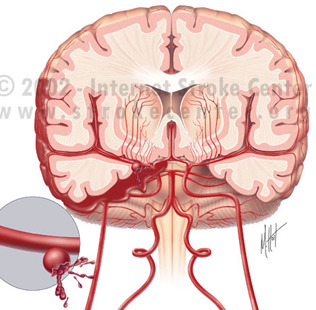

지주막하출혈은 뇌를 덮고 있는 지주막하 공간에 갑작스러운 출혈이 발생하는 질환으로,

응급상황을 초래할 수 있는 심각한 상태입니다.

주로 뇌혈관의 파열로 인해 발생하며, 적절한 치료가 이루어지지 않으면

- 뇌동맥류

가장 흔한 원인으로 꼽히는 뇌동맥류는 뇌혈관 벽이 약해져 부풀어 오르는 상태를 말합니다. 압력에 의해 동맥류가 터질 경우, 혈액이 지주막하 공간으로 유입되며 출혈이 발생합니다. - 혈관기형(AVM, Arteriovenous Malformation)

동맥과 정맥이 비정상적으로 연결된 상태로, 혈관 벽이 약하여 출혈 가능성이 높습니다.